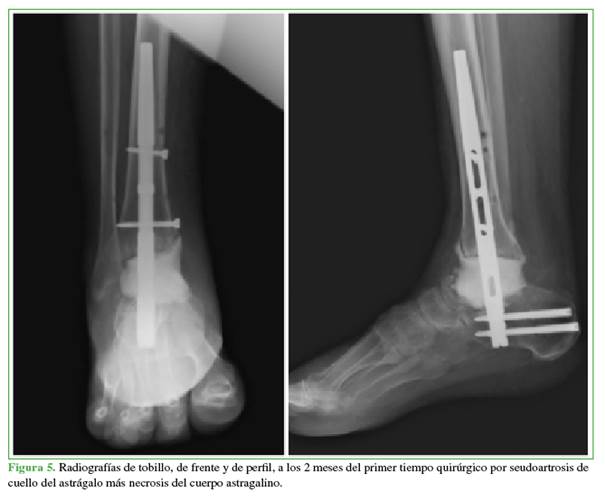

En los controles radiográficos periódicos y excepcionales por la persistencia del dolor, se detectó la seudoartrosis de la fractura del cuello del astrágalo asociada a necrosis ósea avascular del cuerpo astragalino y la falta de consolidación de la artrodesis subastragalina, además, del desarrollo de artrosis tibioastragalina.

Se estabilizó el calcáneo con la tibia por medio de un clavo tibiocalcáneo retrógrado manteniendo la longitud del miembro y rellenando el defecto con dos dosis de cemento con 2 g de vancomicina por dosis (Figura 5). En los cultivos, se aisló Staphylococcus epidermidis en el tejido óseo de tibia distal.